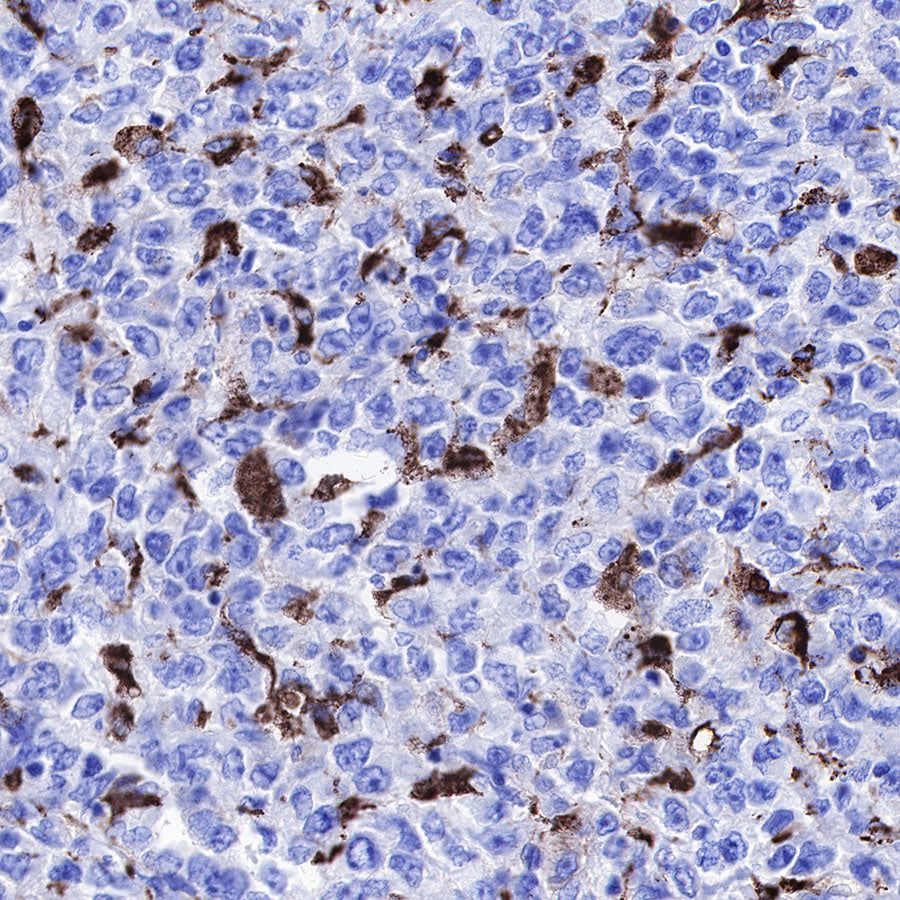

IHC shows positive staining in paraffin-embedded human diffuse large B-cell lymphoma. Anti-CD68 antibody was used at 1/1000 dilution, followed by a HRP Polymer for Mouse & Rabbit IgG (ready to use). Counterstained with hematoxylin. Heat mediated antigen retrieval with Tris/EDTA buffer pH9.0 was performed before commencing with IHC staining protocol.